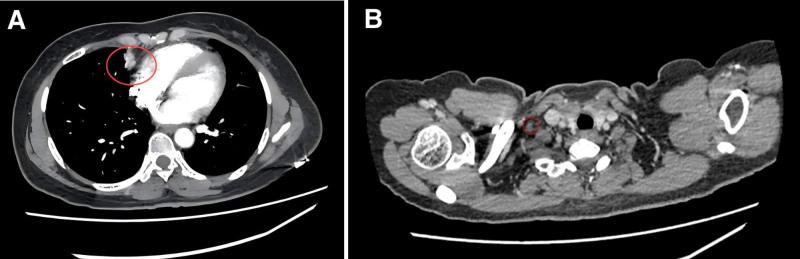

The patient initially received first-line treatment with pembrolizumab combined with docetaxel and nedaplatin, achieving partial response. After progression, second-line therapy included gemcitabine and cisplatin chemotherapy with synchronous radiotherapy, followed by camrelizumab and anlotinib. Regular imaging follow-ups guided therapy adjustments, including extended dosing intervals for camrelizumab during disease stabilization.

Over 4 years of treatment, the patient achieved durable partial response, with significant reduction in tumor burden and no new metastases. As of the most recent follow-up, the patient exhibited an overall survival of 59 months and progression-free survival of 51 months for second-line therapy, with manageable adverse effects including secondary hypothyroidism and grade 2 hypertension.

患者最初接受帕博利珠单抗联合多西他赛和奈达铂的一线治疗,达到部分缓解。进展后,二线治疗包括吉西他滨和顺铂化疗同步放疗,随后是卡瑞利珠单抗和安罗替尼。定期影像学随访指导治疗调整,包括在疾病稳定期间延长卡瑞利珠单抗的给药间隔。

结果